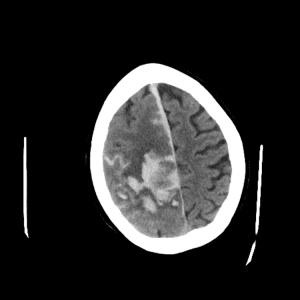

Deep venous infarct

cerebral edema